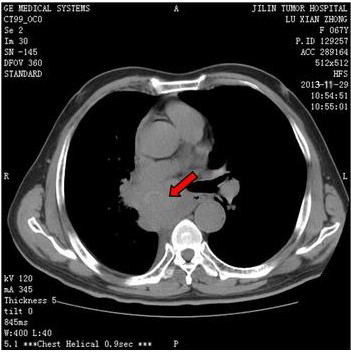

双锁骨上淋巴结肿大分别达6.0cm和4.0cm,质硬如骨骼、固定、无压痛,ECT示左肩胛骨、右股骨中下段骨代谢异常活跃,胸部CT发现两肺转移。

治疗3周期后双锁骨上淋巴结明显缩小,4周期后双锁骨上淋巴结接近消失,两肺转移灶明显减少或缩小,左肩关节疼痛消失,声音嘶哑无变化。疗效评价为部分缓解(PR)。